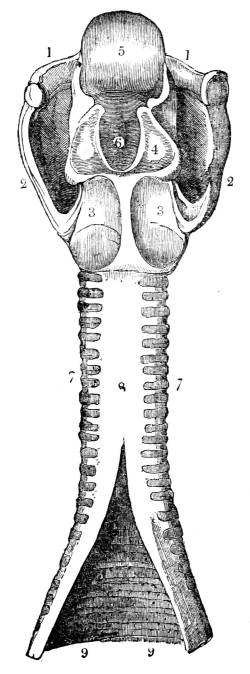

Fig. CXXXVI.—

Posterior View of the Larynx and

Trachea.

1. The os hyoides. 2. Thyroid cartilage. 3. Cricoid

cartilage. 4. Arytenoid cartilages, separated from each other.

5. Epiglottis. 6. Opening of the glottis. 7. Termination of the

cartilaginous rings of the trachea. 8. The ligamentous portion of the

trachea. 9. Trachea laid open, showing its internal mucous surface

and follicles, with the anterior portion of the cartilaginous rings

appearing through it.

362. The first portion of the windpipe called

the larynx (figs. CXXXV. and CXXXVI. ), constitutes

the organ of the voice. It is situated at the upper

and fore part of the neck (fig. CLIII. 7, 9), immediately

under the bone to which the root of the40

tongue, called the os hyoides (figs. CLIII. 6, and

CXXXVI. 1), is attached. The larynx forms a

very complex structure, and is composed of a41

variety of cartilages, muscles, ligaments, membranes,

and mucous glands (fig. CXXXVI. 2, 3, 4,

5). At its upper part is a narrow opening of a

triangular figure called the glottis (fig. CXXXVI.

6), by which air is admitted to and from the lung.